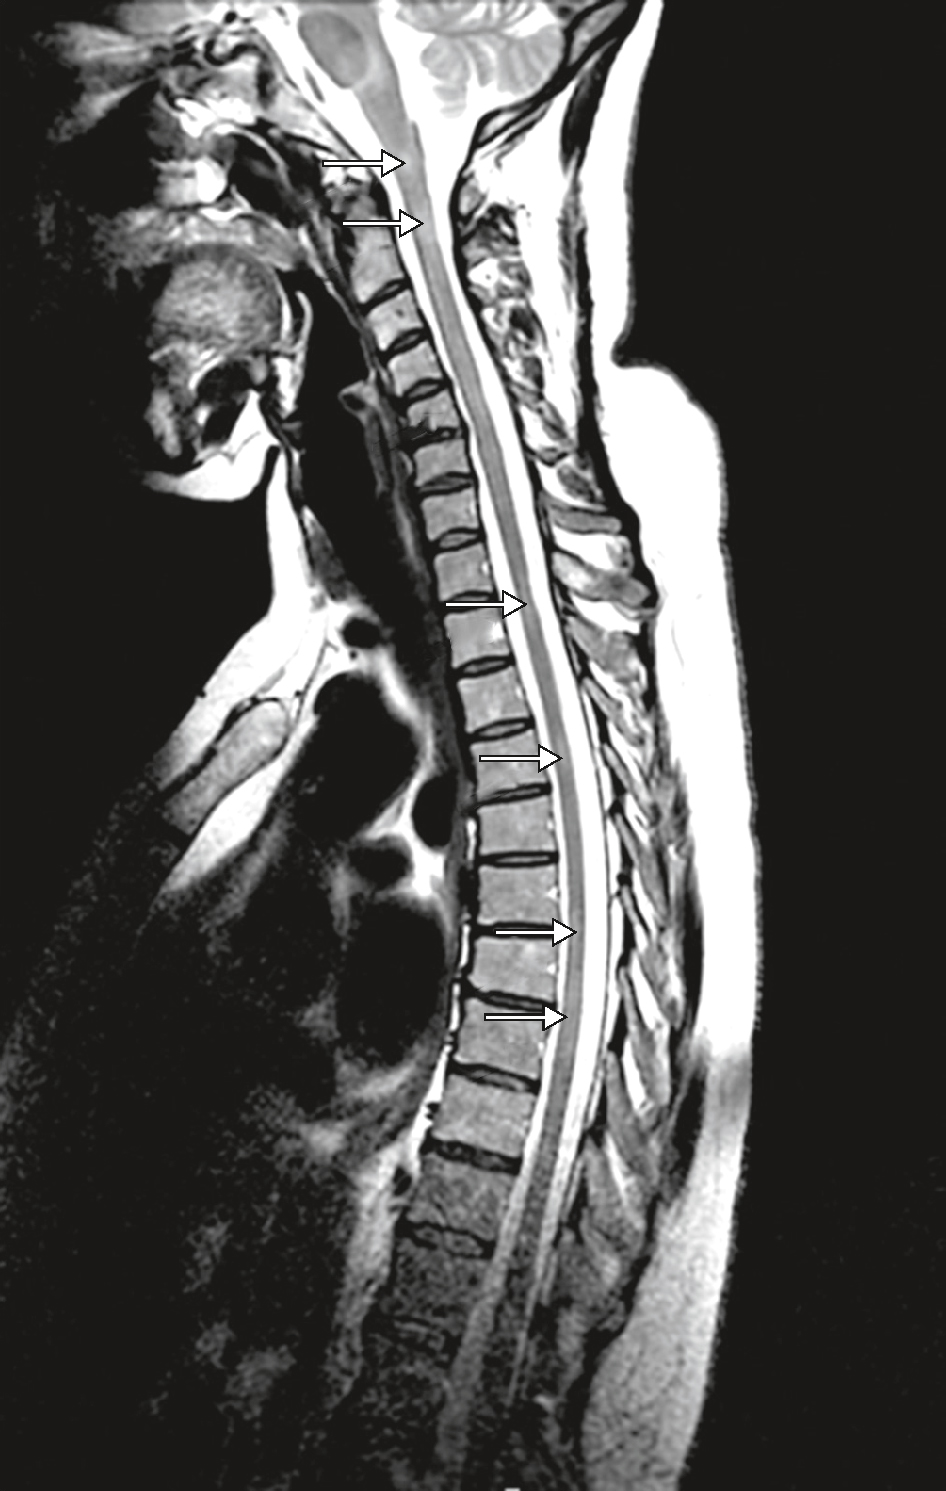

Imagerie médullaire dans la sclérose en plaques. IRM en séquence T2 : multiples hypersignaux le long de la moelle cervicodorsale (flèches).

L'imagerie médullaire dans la sclérose en plaques (SEP) montre des lésions caractéristiques sur une IRM de la moelle épinière. Sur une vue sagittale, on peut observer la moelle épinière entourée par les vertèbres. Les plaques de démyélinisation, qui sont des zones où la myéline, la gaine protectrice des fibres nerveuses, a été détruite, apparaissent souvent comme des zones hyperintenses sur l'image. Ces plaques indiquent des dommages aux fibres nerveuses, perturbant la transmission des signaux entre le cerveau et le reste du corps. L'IRM est essentielle pour visualiser ces lésions et diagnostiquer la SEP. Elle permet également de surveiller la progression de la maladie et l'efficacité des traitements. Les lésions peuvent varier en taille et en emplacement, et leur visualisation aide les médecins à comprendre l'étendue de la maladie et à adapter les stratégies thérapeutiques en conséquence. En résumé, l'imagerie médullaire dans la SEP montre des lésions hyperintenses sur la moelle épinière, reflétant des zones de démyélinisation et de dommages nerveux, cruciales pour le diagnostic et la gestion de la maladie.